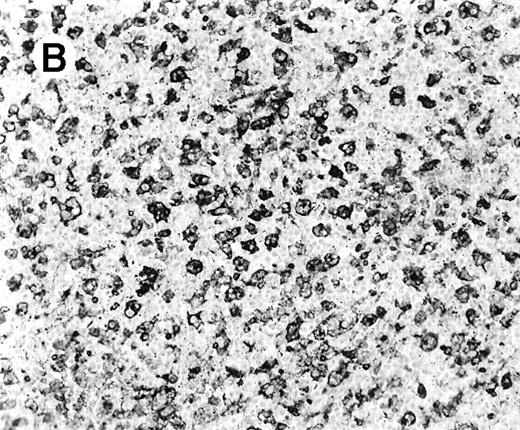

All cases showed essentially similar histologic findings in the liver and spleen. The splenic white pulp was inconspicuous to markedly depleted, whereas the sinusoids showed a prominent lymphoid infiltration (Figure 1A). There was striking hemophagocytosis within the splenic sinusoids (Figure 1B). The infiltrating lymphocytes were small and lacked significant cytologic atypia (Figure 1B). Immunoblasts and plasma cells were not prominent. The liver had prominent portal as well as sinusoidal infiltrates of small lymphocytes morphologically identical to those noted in the spleen (Figure 2). There was intracellular and intracanalicular cholestasis, steatosis, and focal necrosis. Hemophagocytosis was present within the sinusoids. In case 5, the spleen showed extensive areas of necrosis mainly in the perifollicular and periarteriolar lymphoid sheaths of the white pulp with the presence of immunoblasts reminiscent of IM.

Histologic findings in the liver.

(A) Liver specimen from case 1 shows prominent portal and sinusoidal lymphoid infiltrate (hematoxylin and eosin, × 200). (B) The infiltrating lymphocytes are small and lack cytologic atypia (hematoxylin and eosin, × 600).